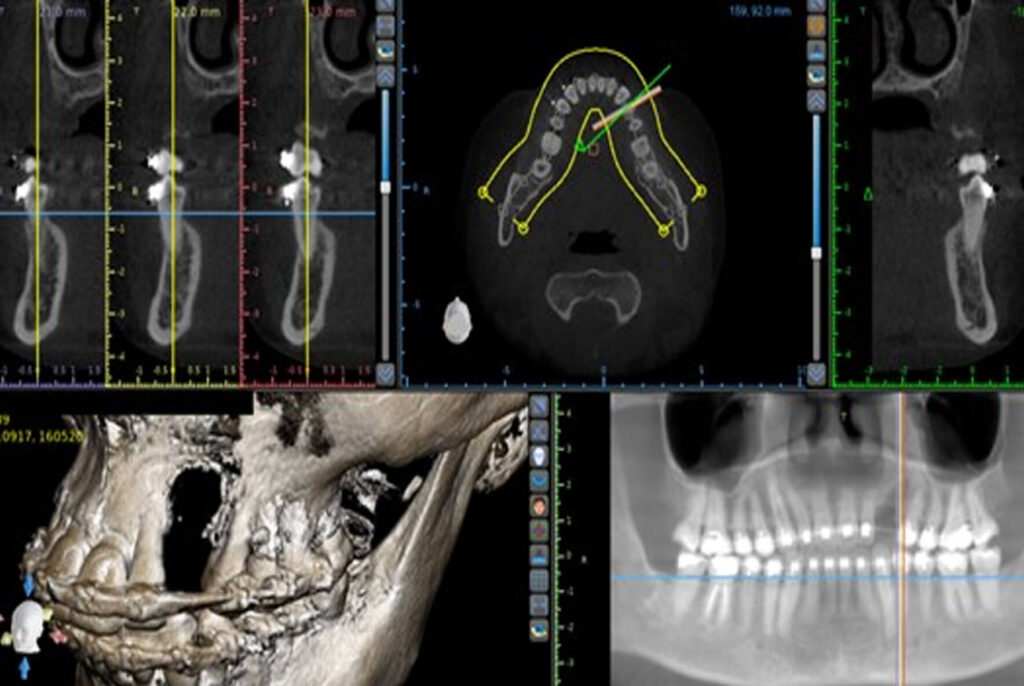

A 30-year-old female patient was referred for an implant restoration in the left upper canine area. In order to acquire a

precise assessment of the tridimensional bone volume, a Cone Beam CT scan was taken which revealed a vertical osseous deficiency (fig 1). Prior to the implant installation a surgical vertical augmentation became necessary so that the

implant could be placed in a tridimensional correct position (fig 2).

Figure 1 – CT scan showing vertical

deficiency.